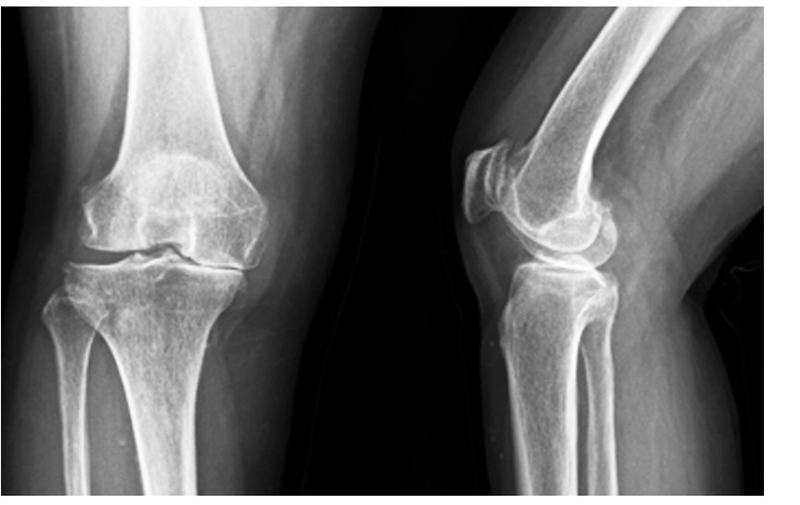

(2)65岁女性患者,以右膝关节疼痛3年、加重半年为主诉入院,入院查体右下肢内翻畸形8°,膝关节内侧间隙压痛阳性,外侧无压痛,浮髌试验阴性,髌骨研磨试验 阴 性,抽 屉 试 验 阴 性,ROM10°~130°,诊断为右膝关节前内侧骨关节炎,行 Oxford活 动 平 台 内 侧 单髁置换术。术后24h内间断 冰 敷,给予预 防 感 染、消 肿 止 痛及抗凝 治 疗,术 后24h康复师指导助行器辅助下床活动,术后1个月膝关 节 HSS评 分 由62分升至81分,KSS评 分 由50分升至85分,内侧疼痛消失,手术效果良好。手术前后影像学资料见图3~4。

图3术前 X线片示内侧间隙呈骨对骨改变